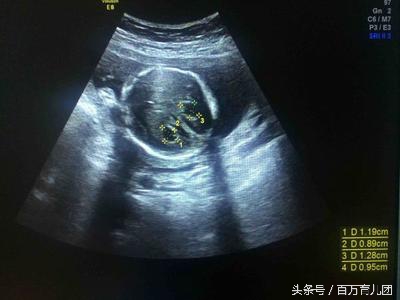

我宝宝第19周时因为要准备唐氏塞查的B超,所以检查了彩超,之前每次检查都很健康的,可是这次检查时大夫却一脸严肃,告诉我孩子左侧脉络丛囊肿!

主任拿着我的单子看了看说:“这正常,单侧脉络丛囊肿是胎儿14周到26周时常见现象,一般26周之后就会消失,不消失反而增大的很少,而且通常伴有其他畸形,你家孩子挺健康,而且是单侧没事的。一般这种情况彩超都不会写出来的。”